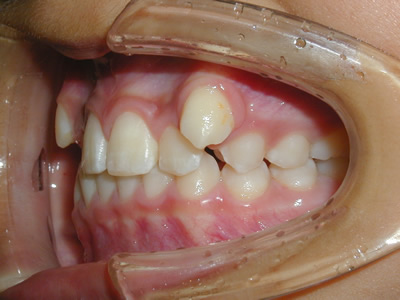

上顎の劣成長 (成長不足) による反対咬合で、上顎は拡大装置と上顎前方牽引装置を併用し前方方向への成長を促して前歯の咬み合わせを改善した後に、上下顎の前歯をマルチブラケット装置で並べました。治療の期間は2年でした。

初診時